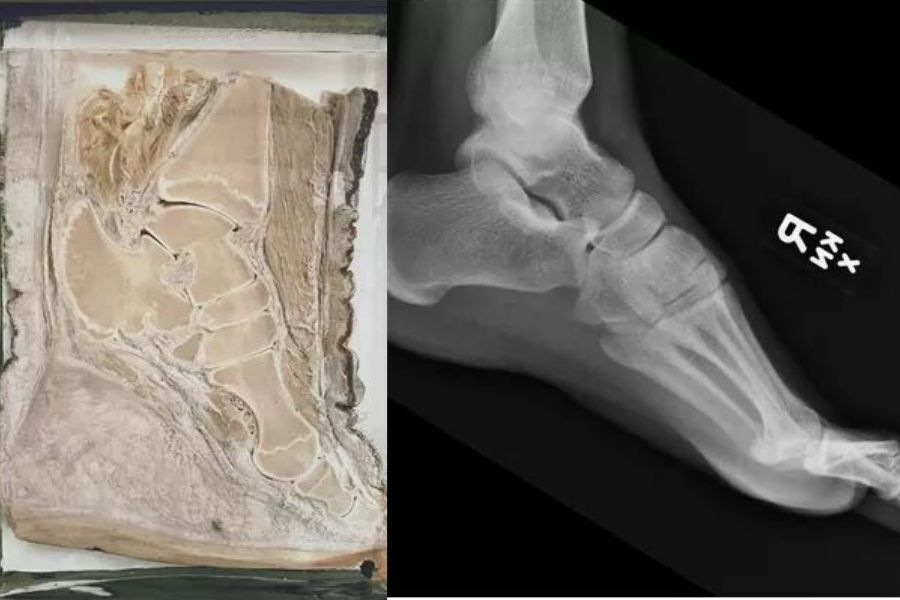

After Breaking His Heel Three Months Ago, His Left Calf Looked A Lot Different

left leg and right leg for comparison

This guy's left calf muscle has atrophied since he broke his heel three months ago and this just shows how much work our muscles truly do.

We use them every day and it's not often we think about them, but if we stop using them we lose them.